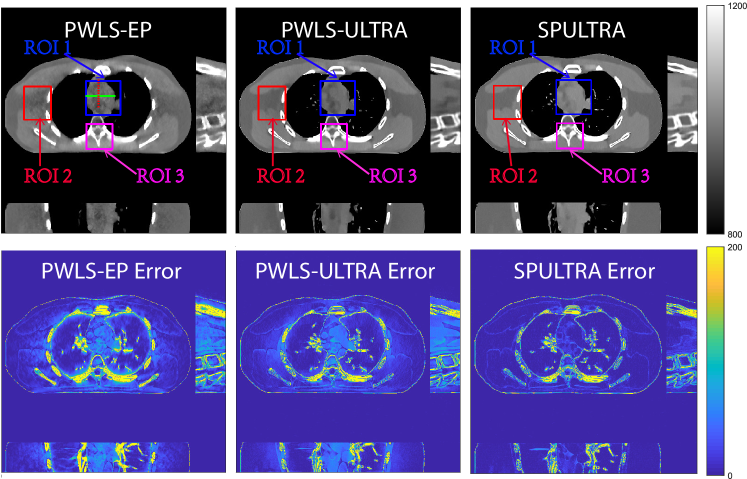

Figure 4: Comparison of reconstructions and reconstruction errors at (a) I0=3×103subscript𝐼03superscript103I_{0}=3\times 10^{3} and (b) I0=2×103subscript𝐼02superscript103I_{0}=2\times 10^{3} dose levels. The 3D images are displayed with the central slices along the axial, sagittal, and coronal directions. The unit of the display windows is HU.

V-A5 Visual Results and Image Profiles

Fig. 4 shows the reconstructed images and the corresponding error images for PWLS-EP, PWLS-ULTRA, and SPULTRA, at I0=3×103subscript𝐼03superscript103I_{0}=3\times 10^{3} and I0=2×103subscript𝐼02superscript103I_{0}=2\times 10^{3}. Compared to the PWLS-EP result, both PWLS-ULTRA and SPULTRA achieved significant improvements in image quality in terms of sharper reconstructions of anatomical structures such as bones and soft tissues, and suppressing the noise. However, the PWLS-ULTRA method introduces bias in the reconstructions, which leads to larger reconstruction errors compared to the proposed SPULTRA method. In Fig. 4, we marked three 3D ROIs in the axial plane, i.e., ROI 1, ROI 2, and ROI 3. Fig. 5 shows the zoom-in images of a 3D plot of ROI 1, and those of ROI 2 and ROI 3 are shown in the supplement. We also plot the evolution of RMSE through the axial slices of the three 3D ROIs in Fig. 6. The figures demonstrate that SPULTRA clearly outperforms the competing PWLS-EP and PWLS-ULTRA schemes.

The above advantages of SPULTRA can be seen more clearly when observing the image profiles. Fig. 7 plots the image profiles for the three methods together with that of the ground-truth image. Fig. 4 shows the horizontal green solid line and the vertical red dashed line, whose intensities are plotted in Fig. 7. It is obvious that the profiles for SPULTRA are closest to the ground-truth among the three compared methods. The gap between the profiles of the PWLS-based methods and the ground-truth shows the bias caused by the compared PWLS methods.